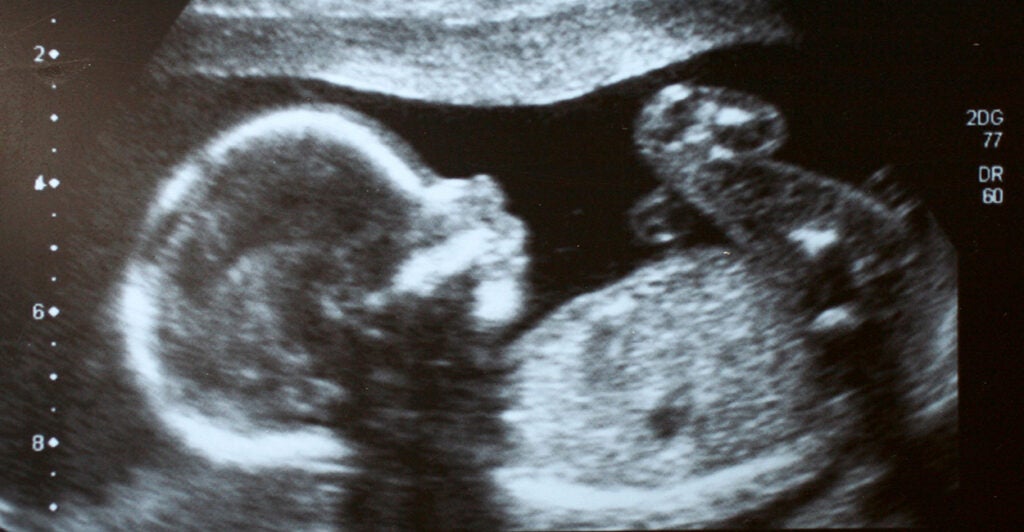

The Heartbeat Protection Act would ban abortions after a heartbeat is detected in an unborn baby, usually around the sixth week of pregnancy.